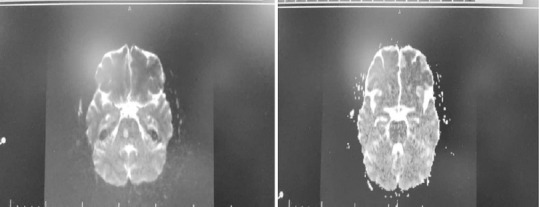

经皮冠状动脉介入治疗和血管造影术后可能会出现核内性眼球震颤(INO)。然而,目前还没有关于桡动脉血管成形术后出现核内眼球震颤的报道。我们报告了一例罕见病例,一名 47 岁男子在桡动脉血管成形术后出现复视。虽然症状在 60 天后得到缓解,但为了减轻患者和医生的焦虑,诊断这种障碍还是很有必要的。

Internuclear ophthalmoplegia (INO) may happen following percutaneous coronary intervention and angiography. However, no reports of INO during radial artery angioplasty were reported yet. We report a rare case in a 47-year-old man presenting with diplopia after radial artery angioplasty. Although the symptoms were resolved after 60 days, diagnosing this obstacle is necessary to reduce the patient and physician's anxiety.